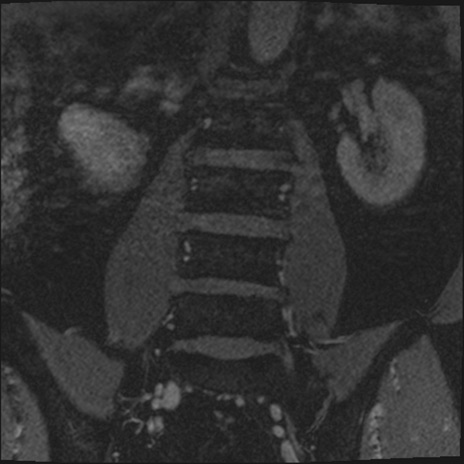

【整形】TIPS症例2 腰椎MRI 3D(冠状断像)

【症例】70歳代男性

【主訴】左下肢痛

【現病歴】2週間前くらいから腰痛、左下肢痛あり。左臀部から大腿、下腿外側のしびれが常時ある。歩行とともに同部位の痛みあり。

【身体所見】Lasegue70-/60+、Bragard-/±、PTR ±/±、ATR -/-、IP 5/5、TA 5/4、TS 5/5、EHL 右第1足趾なし/3、FHL 5/5、hypersthesia(-)、足背動脈触知良好

異常所見と診断は?